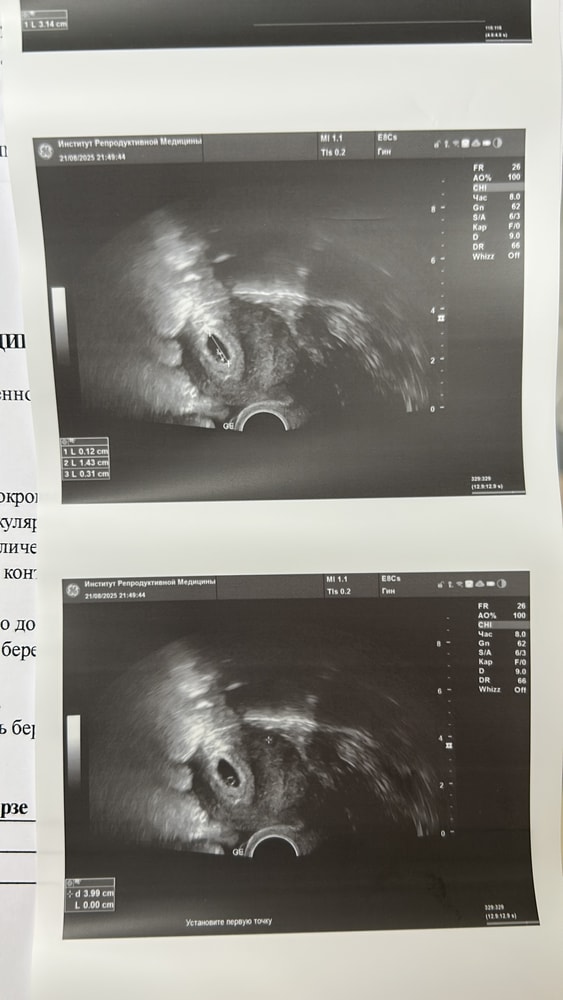

Сходила на узи, ре гов хгч повышен, на правом яичнике желтое тело 31 мм надо гов понаблюдать, а так все нормально

Наш первый снимок 🥰🥰🥰

Просто по снимку будто около 4 мм диаметр. Но у вас даже жм уже есть это наверно потому что хгч высокий.